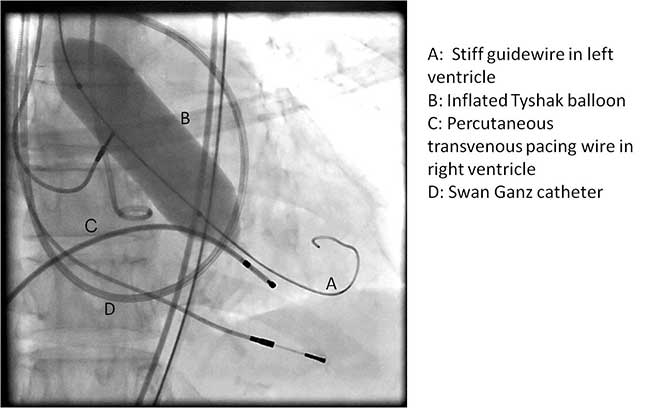

Once optimal C-Arm position has been determined, a small left anterior mini-thoracotomy is made to obtain access to the cardiac apex (Figure 4A, B). Two perpendicular 2-0 prolene pledgeted mattress sutures (or purse string depending on surgeon’s preference) are placed at the apex, taking care not to damage the left anterior descending artery. After the patient is heparinized, the apex is punctured and a guidewire is placed into the left ventricular cavity and advanced through the aortic valve into the aorta under fluoroscopic guidance. Upon confirming position, a 7 French sheath is advanced over the guidewire into the left ventricle and out into the aorta. Using a wire exchange technique under flouroscopy, a stiff guidewire (Lunderquist or Extra-stiff Amplatz) is positioned into the descending thoracic aorta with the aid of a JR4 guide catheter (Boston Scientific Corporation, Massachusetts).

Once the positioning of the valve is confirmed by echocardiography and fluoroscopy, balloon valvuloplasty is performed in a similar fashion to the transfemoral approach described earlier. Upon restoring stable hemodynamics, the mounted Sapien valve on a balloon catheter is introduced transapically and proper position is confirmed by echocardiography and angiography (Figure 4C). For the transapical approach, the recommended position of the prosthesis is 50% of the prosthesis on the aortic side of the aortic annulus and 50% on the ventricular side of the annulus. Since the delivery system is much shorter compared to the transfemoral approach, the direct apical access to the aortic annulus results in less stored torque in the system. Therefore on deployment, the prosthesis does not have the tendency to migrate. During a period of rapid ventricular pacing, the valve is rapidly deployed by expanding the balloon (Figure 5). The valve is not re-ballooned unless there is moderate to severe paravalvular leak. The ventricular sheath is then removed and hemostasis is achieved by tying down the apical purse string sutures during rapid ventricular pacing. Great care must be taken in tying these sutures, as too much tension or torque may cause the ventricular apex to tear and cause uncontrollable bleeding.